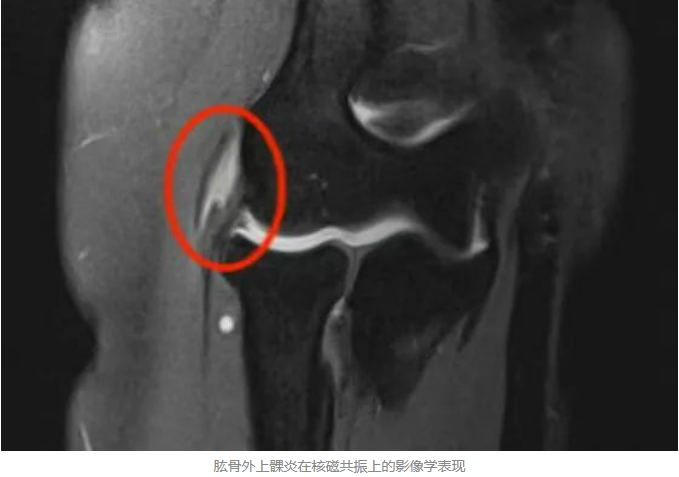

目前,肱骨外上髁炎的病理学主要原因是手肘及前臂反复过度使用导致桡侧腕短伸肌腱的微损伤。

■肘关节镜下治疗顽固性网球肘

肘关节镜属于一种微创治疗,通过2个4mm的入口,在镜头的直视下将引发疼痛的腕短伸肌止点和肱桡关节处的滑膜皱襞进行清理,从根本上治疗肱骨外上髁炎。手术时间约10分钟,创伤小、疗效好,能够在短时间内恢复活动。